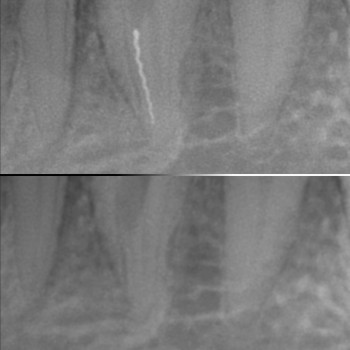

Тільки уявіть, наскільки нечітко проглядаються зубні канали неозброєним оком. А якщо корінь зуба викривлений, то стоматолог діє фактично навмання.

З появою стоматологічного мікроскопа все змінилося. Тепер чистка та пломбування зубних каналів проводиться під наглядом апарата з найвищою точністю.

Це незамінний прилад у стоматології, коли йдеться про повторне лікування зубних каналів після виникнення ускладнень. Зазвичай проблеми виникають через погано очищені та запломбовані канали, випадкове їх пошкодження бормашиною чи залишки сторонніх предметів у каналах зубів, які лікували раніше.